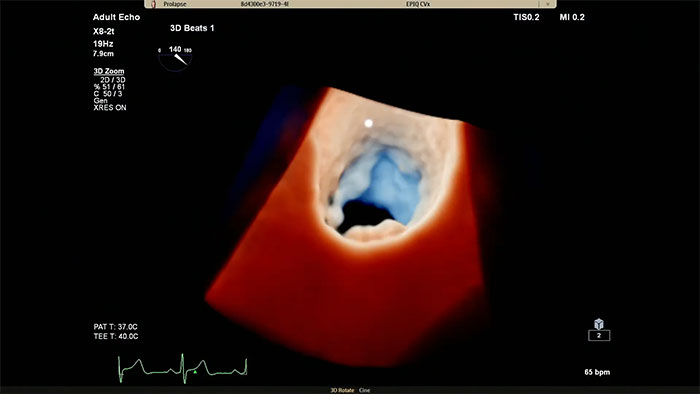

Darstellung der Herzmorphologie mittels Ultraschall mit TrueVue Glass